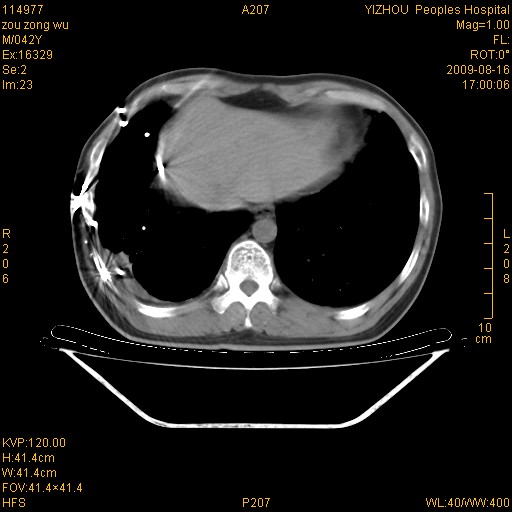

以下是引用zjzjr在2009-8-17 10:42:00的发言:[br]右侧间质性肺炎伴纤维化,右肺下叶肺囊肿伴感染(不除外外伤后引起),右肺野及胸壁软组织\\肝内见多发斑点状,中枪了吧.右侧胸膜肥厚\\粘连.